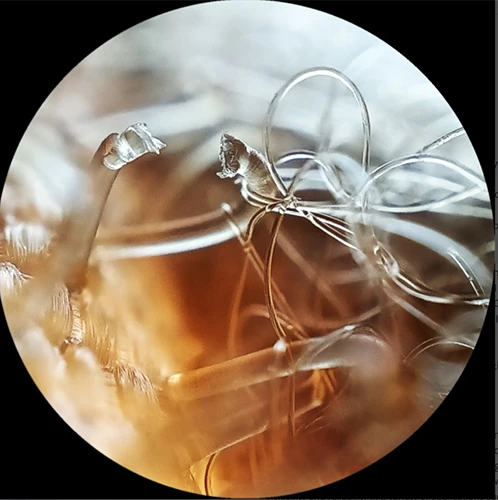

• Galeri

Galeri